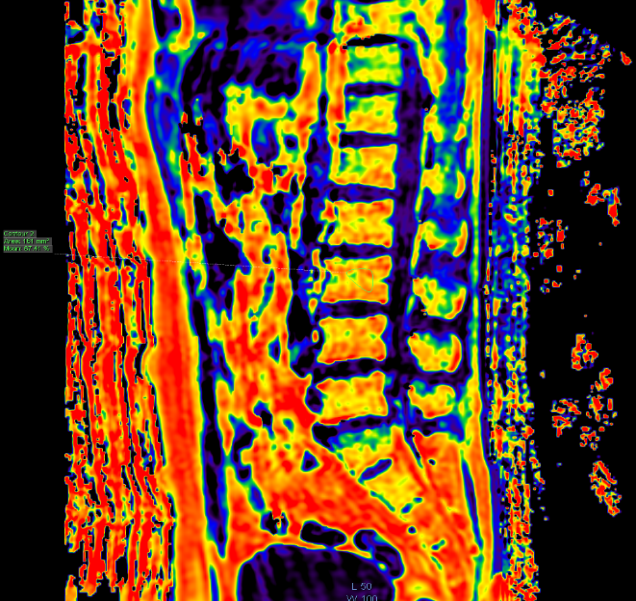

脂肪定量是临床最多使用的,除了用在肝脏上,还可用在骨骼肌方面,比如通过测量椎骨的脂肪分数来判断骨质疏松。

在骨骼肌中,脂肪定量用途也十分广泛。包括:测定冈上肌脂肪性退变程度;测定椎体脂肪含量评估骨质疏松情况;评估化疗后骨盆脂肪含量....。